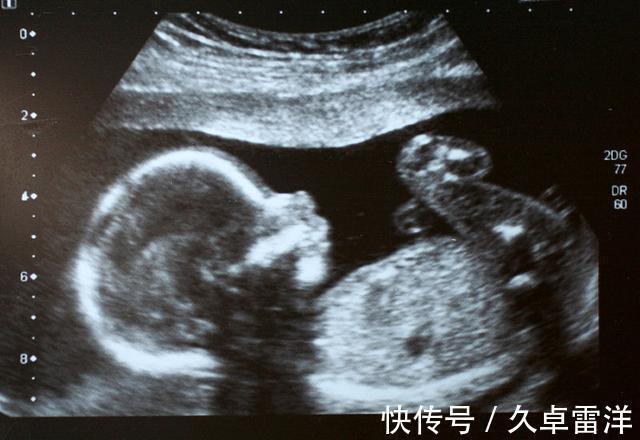

产检一切正常,胎儿出生之后却是畸形由于工作的关系,再加上眼光比较高,王敏结婚时间比较晚,一直到33岁才结婚,第二年怀孕。身为高知识分子,王敏很清楚自己这个年龄怀孕属于高危活动,毕竟年龄上离大龄产妇仅一步之遥,众所周知,大龄产妇不论是母体还是宝宝都有很大可能出现问题。在这样的情况下,王敏极度重视胎儿的健康状况,平日里这个不敢吃,那个不敢碰,而且没事就去做产检。发展到后期,就连她爱人都觉得妻子有点神经质,毕竟就算是正常人一直做体检,迟早也会出现问题,何况是身体处于特殊时期的孕妇?

面对爱人的质疑,王敏很冷静,她说自己很清楚自己在做什么,这并不是发疯,也不是没事找事。在她看来,虽然经常去产检显得不太正常,但至少目前为止,医生没有说做检查会危及胎儿,但大龄产妇的高危性却已经得到了公认,她宁可相信已经得到证实的东西。本来一切都很好,产检结果正常,王敏的身体状况也没异状,就在全家人等着庆祝时,让所有人都想不到的情况发生了——居然是畸形儿!对此,王敏表示完全无法接受,她觉得自己花了那么多时间、精力以及金钱去做产检,就是为了避免出现这样的问题。检查时医生明明表示什么问题都没有,现在却变成这样,医院必须承担责任。王敏还表示,她也不是不讲道理的人,如果是基因方面的遗传性疾病,她也就自然倒霉了,毕竟这种疾病本来就不好检查出来,但畸形儿问题又不是什么疑难杂症,通过现代科学技术完全可以提前预测,这很明显是医院方面在工作上出了岔子。